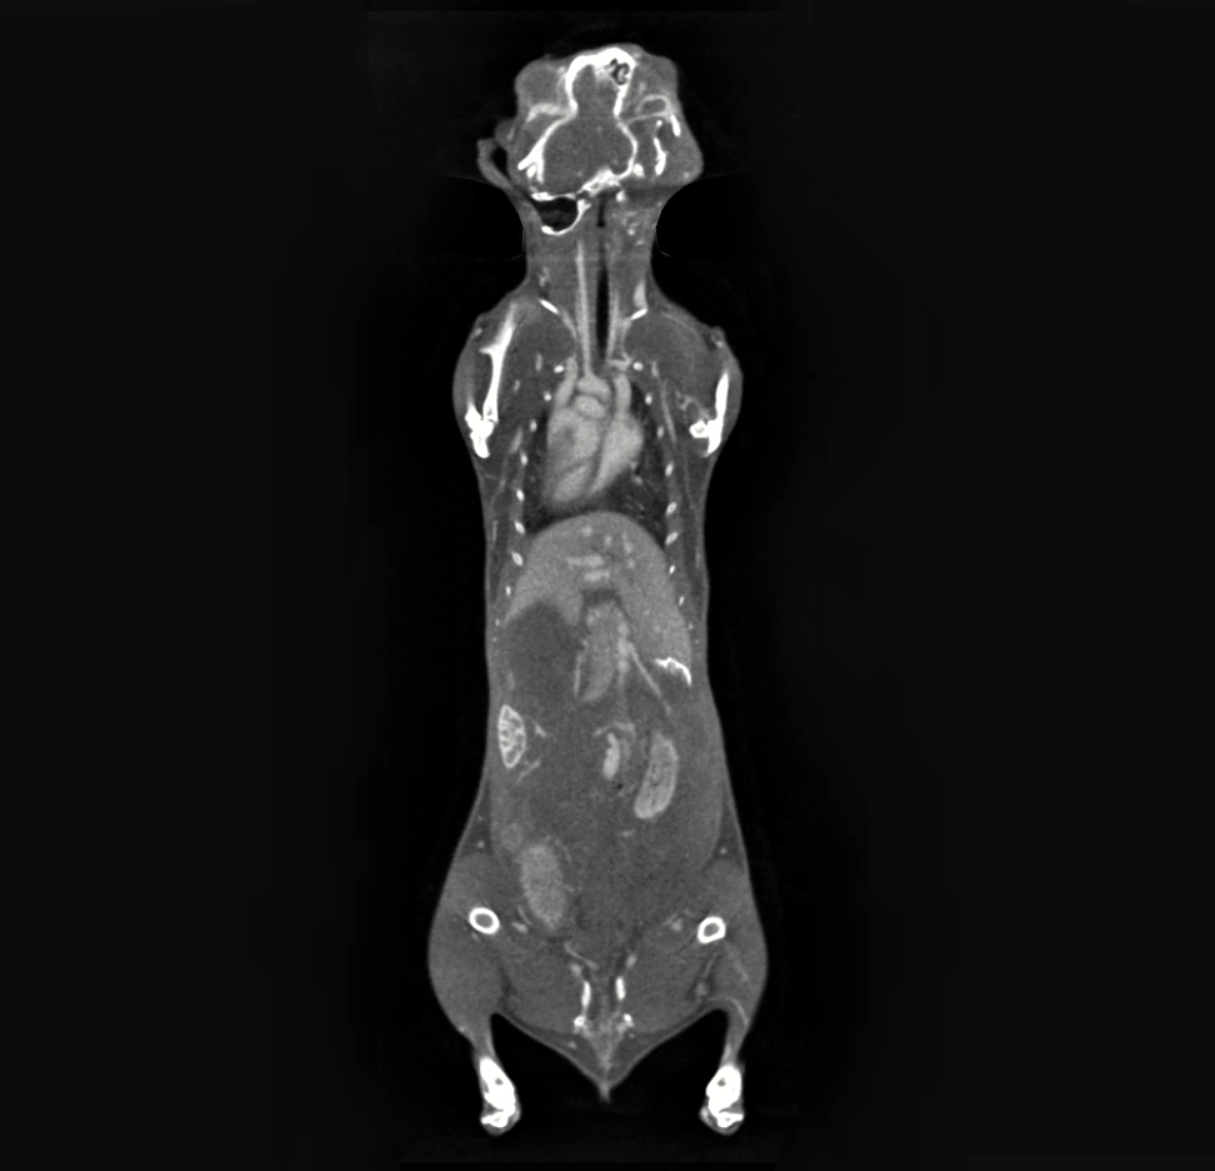

碘基造影剂经小鼠尾静脉注射后,使用IMAGING 100对腹部区域进行动态扫描,结果清晰显示腹主动脉的走行、管腔形态、管径大小及周围组织结构。

▲超高分辨率·离活一体Micro-CT(型号:IMAGING 100)